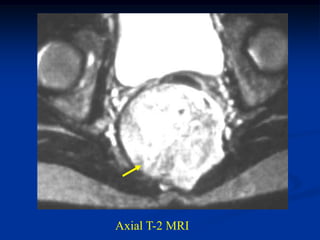

Case #1096

18 year male with

adamantinoma tibia

Bone scan

Sagittal T-2 MRI

Axial T-2 MRI